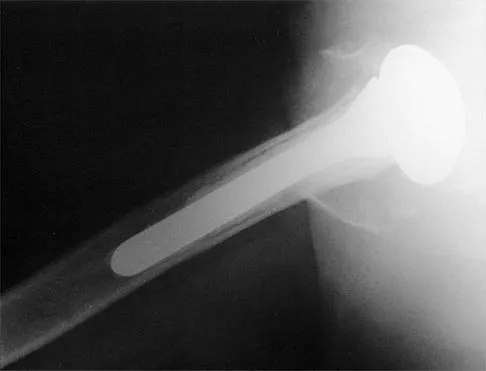

A 62-year-old man with a long history of right shoulder pain and weakness is scheduled to undergo hemiarthroplasty. Based on the radiographs shown in Figures 6a through 6c, what preoperative factor will most affect postoperative functional outcome?

Explanation

The radiographs reveal osteoarthritis and proximal humeral head migration. Integrity of the rotator cuff must be questioned based on these radiographic changes. The status of the rotator cuff is the most influential factor affecting postoperative function in shoulder hemiarthroplasty. The coracoacromial ligament provides a barrier to humeral head proximal migration in the face of a rotator cuff tear. The radiographs do not indicate significant humeral head or glenoid erosion. Acromioclavicular arthritis is often asymptomatic. Iannotti JP, Norris TR: Influence of preoperative factors on outcome of shoulder arthroplasty for glenohumeral osteoarthritis. J Bone Joint Surg Am 2003;85:251-258.